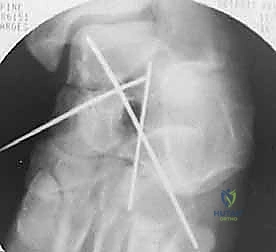

هنا تبدأ المرحلة الأهم: "الرد". باستخدام أدوات دقيقة، يتم إعادة القطع العظمية المكسورة إلى مكانها التشريحي الأصلي بدقة مليمترية. يتم تثبيت القطع مؤقتاً باستخدام أسلاك كيرشنر (K-wires) الدقيقة.

المرحلة الرابعة: التثبيت الداخلي (Internal Fixation)

بمجرد التأكد من أن العظم عاد لشكله الطبيعي تماماً، يتم استبدال الأسلاك المؤقتة بتثبيت دائم. يستخدم الدكتور هطيف أحدث الغرسات الطبية العالمية:

يتم وضع المسامير عادة من اتجاهين (من الأمام للخلف، ومن الخلف للأمام) لإنشاء هيكل ميكانيكي صلب يتحمل الضغوط.